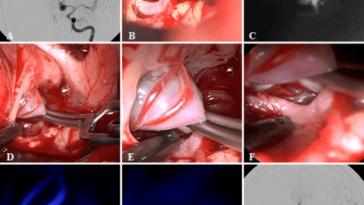

Revolutionizing Craniocervical Dural Imaging with Endoscope Integrated Indocyanine Green Videoangiography

Understanding the Challenges of Craniocervical Vascular Malformations In recent years, the management of vascular malformations at the craniocervical junction has been on the forefront of neurosurgical innovation. This editorial takes a closer look at the evolving techniques that combine advanced imaging technology with minimally invasive procedures, focusing on the role of endoscope‐integrated indocyanine green (ICG) […] More